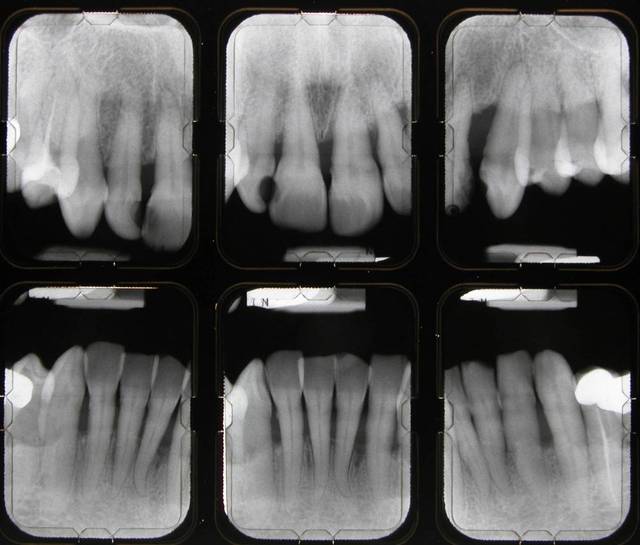

Pour me faire pardonner, je vous envoie le status initial et le bilan de sondage.

La consultation: DSCN 7002

1 mois après la consultation et motivation à l'hygiène: DSCN 7502

Le jour de la lithotriptie: DSCN 7030

6 mois après: DSCN 0013